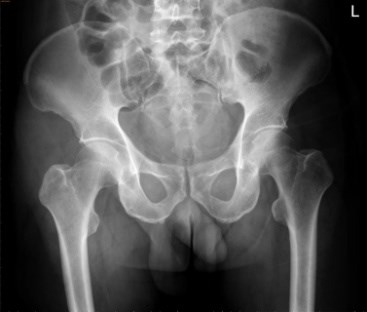

病历资料:该患者为中年男性,因车祸伤致骨盆骨折合并髋外侧及后侧大面积Morel-Lavallee 损伤。

术前影像